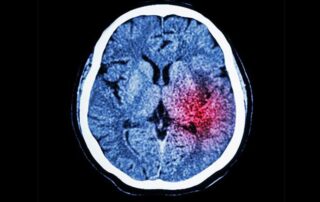

Low Potassium Levels Combined with High Sodium Levels Increase Stroke Risk

A clinical study led by Jorge Polónia showed that besides sodium (found in high amounts in sault), the intake of potassium also influences the onset of a stroke and other cardiovascular problems. However, unlike sodium intake, which should be low, the levels of potassium must be high, explains the doctor and researcher of CINTESIS. The research team aimed at evaluating [...]